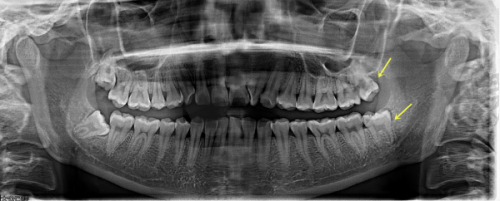

在进行一颗种植牙治疗前,患者需要进行全方面的口腔检查和评估。医生会通过口腔X光、CT等检查手段,了解患者的牙槽骨密度、高度、宽度等情况,同时评估患者的全身健康状况,排除手术禁忌证。根据检查结果,医生会为患者制定个性化的种植方案。

种植体植入手术

在局部麻醉下,医生会在患者的牙槽骨上制备一个合适的种植窝,然后将种植体植入其中。手术过程中,医生会严格遵循无菌操作原则,确保手术的安心性。植入种植体后,患者需要等待一段时间,让种植体与牙槽骨形成骨结合,这个过程一般需要3 - 6个月。